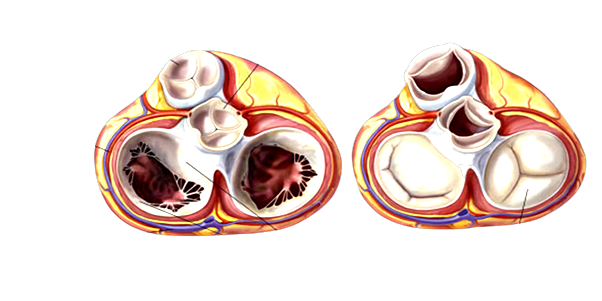

“Questo dato è forse il più allarmante. Oltre a non conoscere queste malattie e i loro sintomi, le persone non sembrano neanche esserne particolarmente interessate o preoccupate, nonostante le forme più gravi possano portare a morte nel giro di 2-3 anni”, commenta Gennaro Santoro, Primario cardiologo interventista, Docente Scuola Superiore S. Anna – Pisa. “Senza creare però allarmismi, è necessario sottolineare che, se diagnosticate tempestivamente, le malattie delle valvole cardiache possono essere curate e, con le cure adeguate, si può riacquistare un`ottima qualità di vita”, chiarisce. A seconda della gravità, i trattamenti variano da quello farmacologico alla cardiochirurgia. “Una valvola cardiaca danneggiata può essere riparata oppure sostituita con un intervento cardiochirurgico, la cui tecnica è andata via via migliorando negli anni con la messa a punto di procedure minimamente invasive, sino alla più recente TAVI, un intervento per sostituire la valvola aortica senza aprire il cuore consentendo di trattare anche persone non indicate per la cardiochirurgia” continua Pierluigi Stefano, Direttore Cardiochirurgia AOU Careggi.

La tempestività è fondamentale per poter curare le malattie delle valvole cardiache. Stenosi e insufficienza valvolari possono compromettere la funzionalità del muscolo cardiaco, portando a grave scompenso cardiaco. È necessario intervenire prima che questo si verifichi, altrimenti la disfunzione potrà divenire progressiva, con esito letale. “Purtroppo, i segnali di queste malattie sono poco evidenti, soprattutto negli stadi iniziali e nelle forme meno gravi, e spesso imputati alla “vecchiaia” e per questo molto spesso trascurati. È però necessario che le persone li sappiano riconoscere per poter procedere ad una accurata diagnosi; tra i principali ci sono affaticamento, fiato corto, dolore al petto, battito cardiaco irregolare” descrive Silvio Festinese, Cardiologo Consigliere SUMAI Assoprof e Docente in Metodologia medico-scientifica e Farmacologia presso Facoltà di Medicina “Sapienza” Università di Roma. Una volta riconosciuti i sintomi la diagnosi è semplice. “La prima cosa da fare – spiegano al Sindacato Nazionale Autonomo Medici Italiani – è rivolgersi subito al proprio medico di famiglia che con il semplice impiego dello stetoscopio può rilevare un eventuale soffio cardiaco, che costituisce il primo indicatore di queste malattie. Successivamente, per avere conferma, si procede con ulteriori esami, quali un elettrocardiogramma, un`ecocardiografia e un consulto specialistico”.